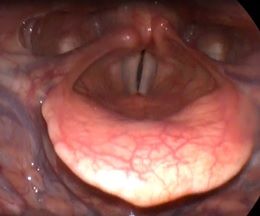

Рис 2В Двусторонний паралич гортани. 1 месяц после операции